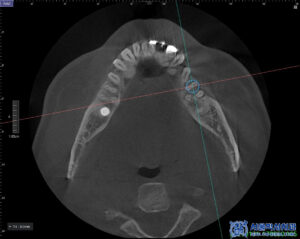

발치 전 CT를 촬영하여

잇몸과 치아 주위의 뼈 상태를

정밀히 파악한 후,

발치가 필요한 치아와 그 주변 구조에 대한

상세한 정보를 얻을 수 있었습니다.

이를 바탕으로 발치 후 임플란트를

식립할 위치와 각도를 정밀하게

계획하였습니다.

이후 무절개임플란트를

진행하였습니다.

본원에서는 무절개로 임플란트를

진행하고 있으며,

컴퓨터 분석을 통해 미리 식립 위치를

시뮬레이션하여 식립 오차를 줄이며,

부기가 많이 없고 회복이

빠른 장점이 있습니다.